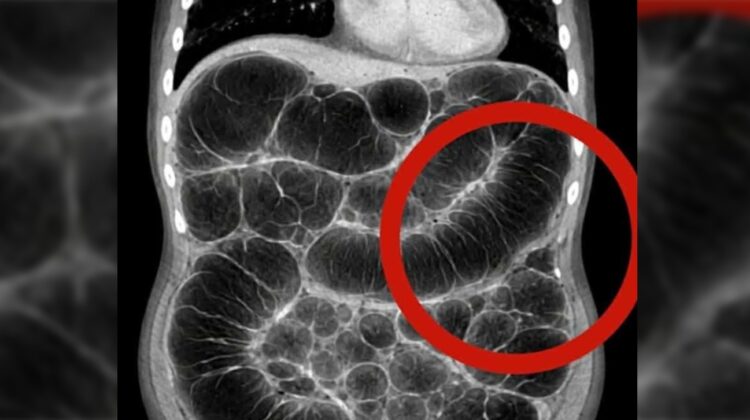

3. Small Intestinal Bacterial Overgrowth (SIBO)

Another important factor is SIBO, where bacteria grow in parts of the intestine where they shouldn’t. These bacteria ferment food excessively, leading to increased gas production. This imbalance often causes persistent bloating and discomfort after eating.

7. Underlying Digestive Conditions

Conditions like gastritis, gut microbiome imbalance (dysbiosis), or irritable bowel syndrome (IBS) can worsen gas-related symptoms. These disorders interfere with how food is processed, increasing fermentation and gas production.